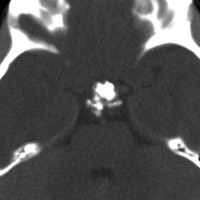

この子の症状は頭痛だけ。両親はなぜ気づかなかったのかと疑問を持ちますが,巨大になるまで症状が出ないこともあるのです。左のCTで腫瘍の周囲にバラバラと白い点状の石灰化があるので診断できます。左の視床下部から発生したクラニオでした。開頭手術しますが超高難易度です,怖いです (┯_┯) 複数回開頭手術になりましたが結果的に全摘出できています (by Dr 山本哲哉)。